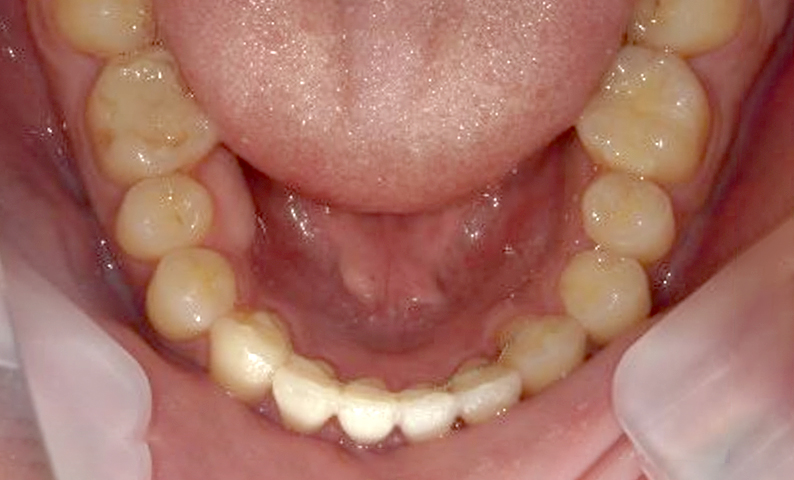

| 治療前 | 治療後 |

|---|---|

|